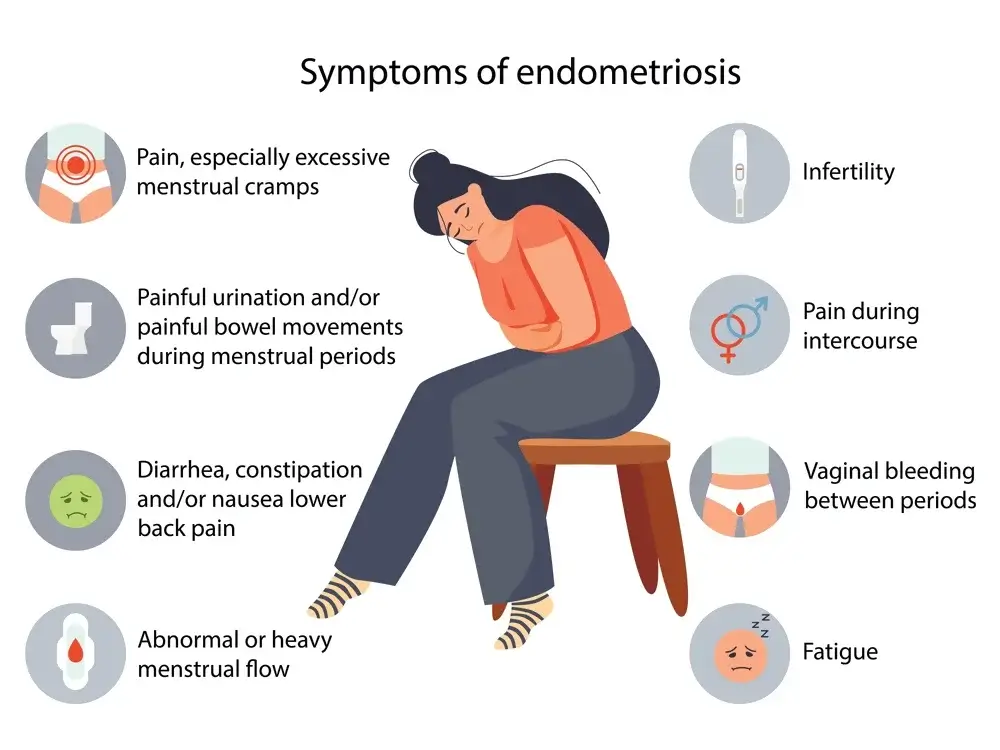

Endometriosis Symptoms and Signs:

Endometriosis is a condition that affects women’s health and is characterized by the growth of endometrial tissue outside of the uterus. This tissue, which normally lines the inside of the uterus, can cause painful symptoms such as heavy bleeding during menstruation and pain during intercourse. Endometriosis can also cause infertility in some women. It is estimated that 1 in 10 women in reproductive age suffer from endometriosis, although this may be an underestimate since many cases are misdiagnosed or not diagnosed at all.